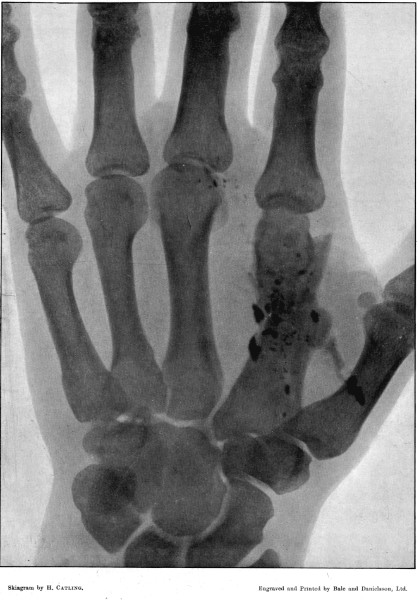

11. Fracture of the Metacarpus, showing Fragmentation of the Bullet194

59. Skiagram of Injury to Interphalangeal Joint 237